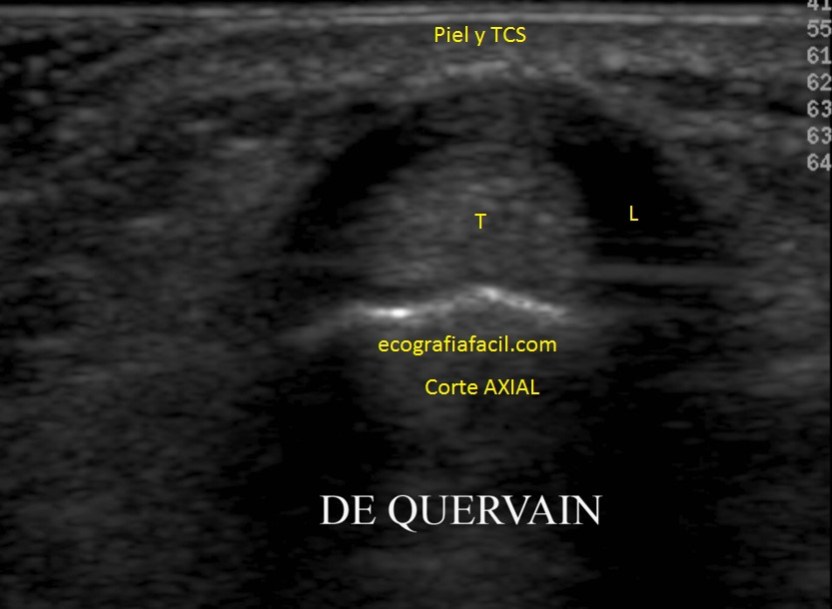

Tendinitis de Quervain:

Tendinitis típica del 1er compartimento de la región extensora de la Muñeca.

• INFLAMACIÓN DE LA CUBIERTA DE LOS TENDONES QUE SE ENCUENTRAN EN EL BORDE RADIAL

Ecográficamente:

Tendón inflamado, hipoecogénico rodeado de líquido, anecoico, que se encontrará en la vaina tendinosa.